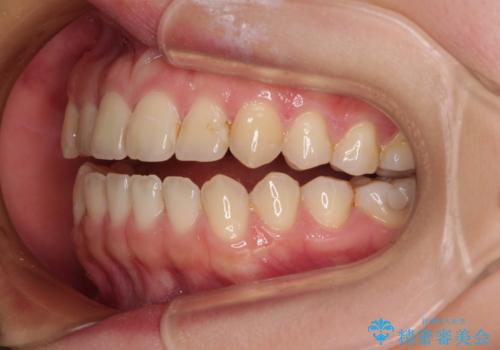

前歯のオープンバイト インビザラインで咬み合わせを改善

- 前歯の開咬を気にして来院された患者様です。

開咬の治療は、前歯を閉じるように動かすとともに、上下臼歯を圧下(骨内にめり込ませる)させることで進めて行きます。

インビザラインは臼歯の圧下を効果的に行えるため、インビザラインを用いて矯正治療を行うこととしました。